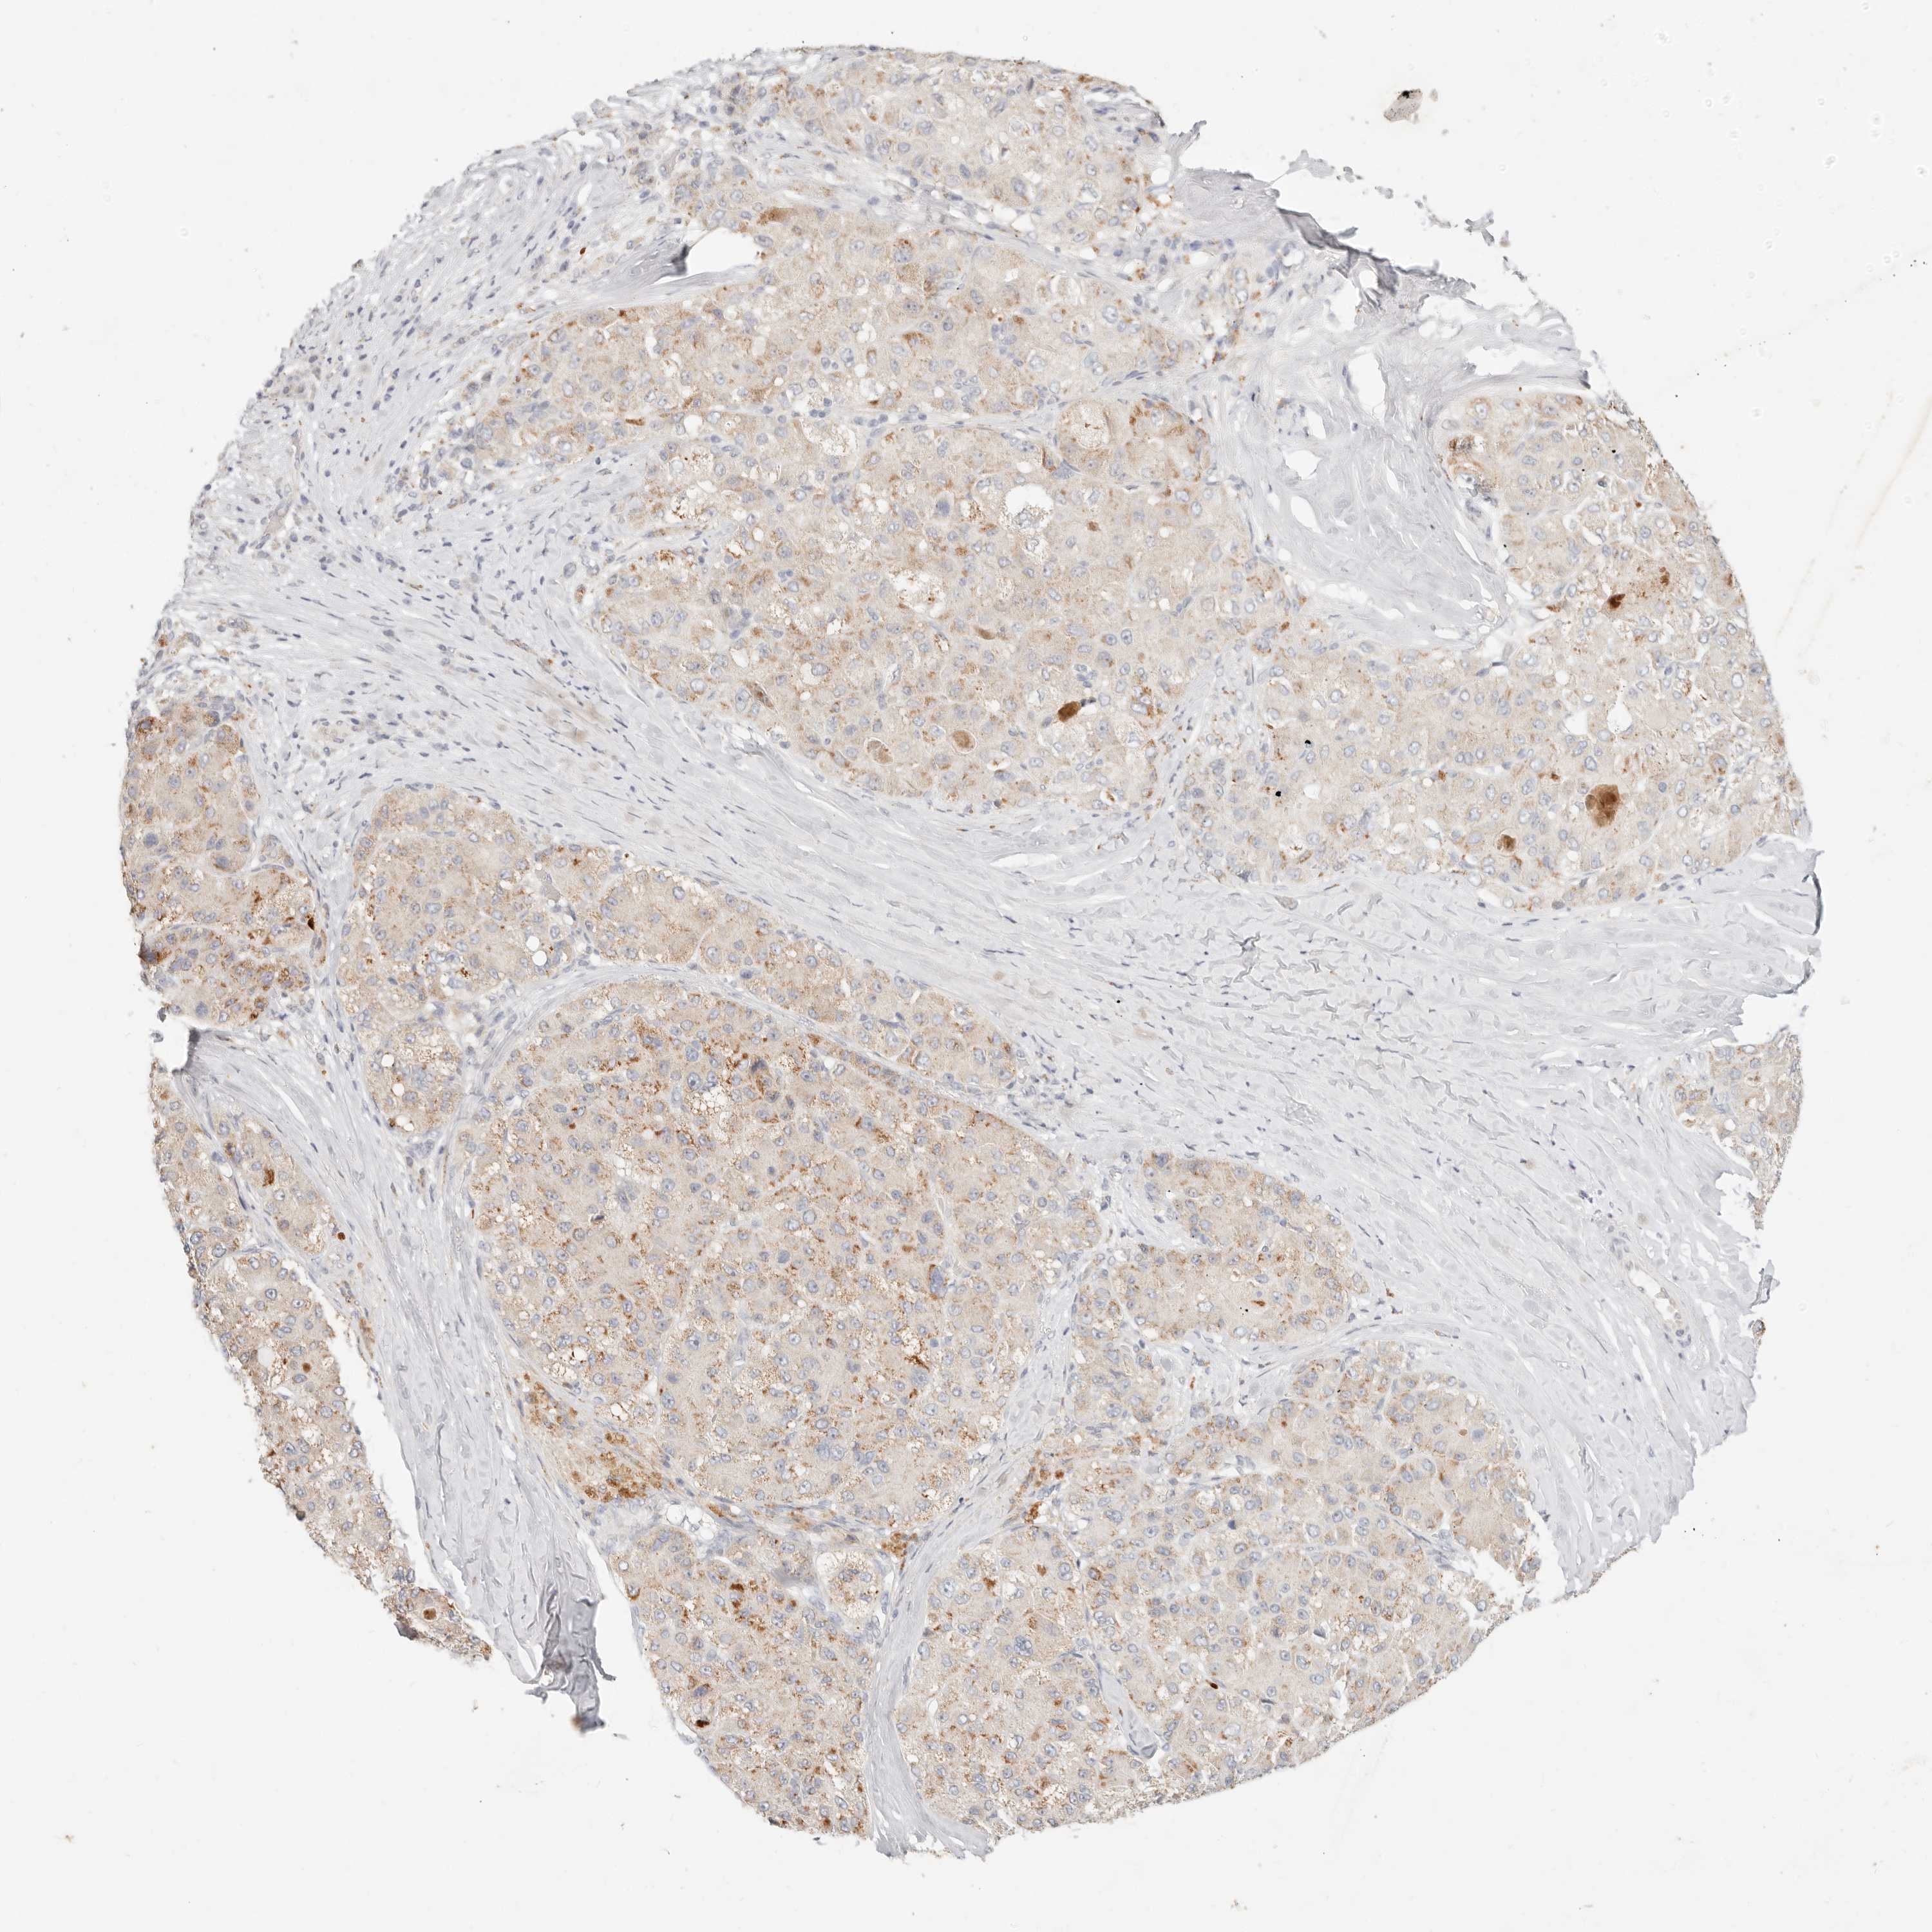

LIVER CANCER - Protein expressioni

A mouse-over function shows sample information and annotation data. Click on an image to view it in a full screen mode. Samples can be filtered based on level of antibody staining by selecting one or several of the following categories: high, medium, low and not detected. The assay and annotation is described here.

Note that samples used for immunohistochemistry by the Human Protein Atlas do not correspond to samples in the TCGA dataset.

Antibody stainingi

Antibody staining in the annotated cell types in the current human tissue is reported as not detected, low, medium, or high, based on conventional immunohistochemistry profiling in selected tissues. This score is based on the combination of the staining intensity and fraction of stained cells.

Each image is clickable and will lead to virtual microscopy that enables deeper exploration of all samples and also displays staining intensity scores, fraction scores and subcellular localization as well as patient and tissue information for each sample.

Antibody HPA021192

Antibody HPA021195

Antibody HPA028759

Antibody CAB021094

Staining

High

Medium

Low

Not detected

Intensity

Strong

Moderate

Weak

Negative

Quantity

>75%

75%-25%

<25%

None

Location

Nuclear

Cytoplasmic/membranous

Cytoplasmic/membranous,nuclear

Cholangiocarcinoma

Carcinoma, Hepatocellular, NOS